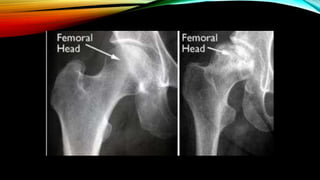

HOW TO DIAGNOSE AVN OF

FEMORAL HEAD?

• Radiograph (X-ray or MRI)

-Ficet and Arlet classification system

1. Symptomatic osteonecrosis + Small lesions + Pre-collape stage

-> Femoral head-sparing procedure

2. Young people + symptomatic osteonecrosis + large lesions + Pre-collapse

stage -> Femoral head-sparing procedure

3. Old people + symptomatic osteonecrosis + large lesions + Pre-collapse

stage ->Total hip arthroplasty

4. Symptomatic osteonecrosis + Post-collapse stage-> Total hip arthroplasty